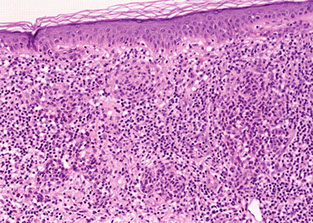

A) Pemphigus vulgaris, B) Pemphigus follicularis with suprabasal epidermal cleavage

Histo: suprabasilar / intraepidermal blister and acantholysis

- "tombstones" - basal keratinocytes that remain attached to BM

IF: IgG and C3 deposition bwt cells in epidermis in fishnet or "chicken-wire" pattern

Pemphigus vulgaris

Autoimmune blistering skin disorder that is NOT pruritic

IgG (IgG1 and IgG4) ab and sometimes C3 against desmosomes (anti-desmoglein, anti-epithelial cell ab, against [Desmoglein 1 and?] desmoglein 3)

Acantholysis: intraepidermal bullae involving oral mucosa